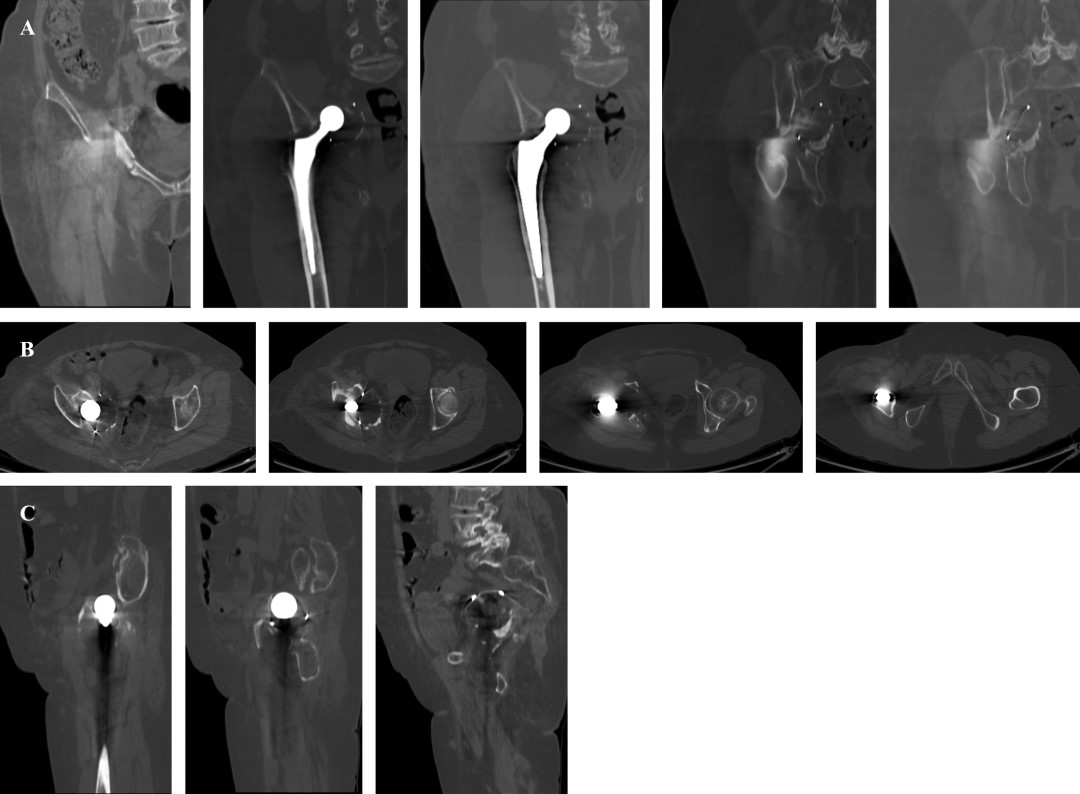

Se realiza abordaje quirúrgico sobre cicatriz previa tipo Hardinge,5 posterior a la profundización de planos se encuentra abundante tejido fibroso. Se realiza capsulotomía y se evidencia migración intrapélvica de componente acetabular y fractura de acetábulo de las dos columnas tipo transversa con defecto óseo acetabular central Paprosky IIIB. Se evidencia líquido intraarticular de aspecto inflamatorio y se descarta infección mediante la prueba de alfa-defensina (Synovasure® defensin) de Zimmer Biomet (Indiana, Estados Unidos). Se procede a la luxación controlada y remoción de componente acetabular y femoral. Se coloca aloinjerto cadavérico de cabeza femoral en fondo acetabular, cubriendo defecto central de tamaño aproximado de 4 × 5 centímetros (Figura 4A); después se coloca la malla metálica previamente moldeada de Zimmer Biomet (Indiana, Estados Unidos) en fondo acetabular (Figura 4B).

Posteriormente, se realiza osteosíntesis de fractura acetabular con placa de reconstrucción de 3.5 milímetros 10 orificios más placa de tercio de caña 4 orificios con tornillos corticales respectivos de DePuy Orthopaedics (Indiana, Estados Unidos). Una vez estabilizado el acetábulo, se coloca cuña de tántalo de 50 × 10 milímetros más dos tornillos de fijación (40 y 35 mm) de Zimmer Biomet en defecto superior acetabular (Figura 5).

Se coloca copa acetabular no cementada Cupule Quattro 50 milímetros de Zimmer Biomet y se verifica estabilidad. Subsecuentemente, se realiza fresado de canal femoral y colocación de cemento óseo previo a inserción de vástago femoral de revisión tipo Arcos 13 × 150 milímetros más cono proximal de Zimmer Biomet. Finalmente, se coloca cabeza femoral de 28 milímetros doble movilidad par de fricción metal polietileno de Grupe Lepine (Genay, Francia).

Se realiza seguimiento clínico y radiográfico a los 30, 60 días y al año, evidenciándose un Harris Hip Score final de 80 puntos y EVA de 0/10. No se evidencia migración medial de componente acetabular, además de adecuada osteointegración de los componentes protésicos (Figura 7).

Figura 4

Figura 5

Figura 6

Figura 7